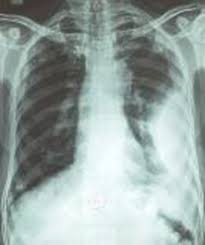

In chf effusions are bilateral and more on right. What are the different appearances of pleural effusion? A loculated effusion has an unusual shape (lentiform) or position in the thoracic cavity. Moreover, it is effective in guiding thoracentesis (thoracocentesis), even in small fluid collections 4. This creates a negative pressure environment in the pleural space, which fills up with fluid, creating a pleural effusion. Tube thoracostomy has variable success in the treatment of complex pleural effusions, with limitations because of viscous fluid, improper tube position or kinking, and, most. In the presence of pleural effusion, the elastic recoil of the lung causes each lobe to retract toward the hilum. Pleural effusions shift the mediastinal structures away from the side opacified. Contrary to the radiological method, ultrasound allows an easy differentiation of loculated pleural fluid and thickened pleura. A prospective study of supine radiographs in 40 patients with pleural effusions showed that effusions with less than 175 ml are unlikely to be detected by this technique. Loculated effusions are difficult to confirm with chest radiograph, but ultrasound, computed tomography (ct), and even magnetic resonance imaging (mri) may be used to verify a localized collection of pleural fluid. Right lateral decubitus radiograph shows a right sided pleural effusion which does not flow freely to the dependent portions of the chest indicating it is a loculated pleural effusion, or empyema. E7.8 loculated effusion loculated effusion.

When pleural malignancy is the underlying cause, pleural nodules or masses may be present. Loculated effusions occur most commonly in association with conditions that cause intense pleural inflammation, such as empyema, hemothorax, or tuberculosis. Contrary to the radiological method, ultrasound allows an easy differentiation of loculated pleural fluid and thickened pleura. More than one half of these massive pleural effusions are caused by malignancy; Discover (and save!) your own pins on pinterest Air within a loculated pleural effusion is usually due to a bronchopleural fistula. On the pa radiograph, the loculated fluid collection manifests with incomplete borders, a radiographic sign of an extrapulmonary lesion, typically of pleural or chest wall origin. Pleural effusion is an accumulation of fluid in the pleural space that is classified as transudate or exudate according to its composition and underlying pathophysiology. The purpose of this study was to assess the value of intrapleural urokinase (uk) instillations in enhancing tube drainage of loculated, complex pleural effusions. This is the appearance of an empyema on a lateral decubitus chest radiograph. Moreover, it is effective in guiding thoracentesis (thoracocentesis), even in small fluid collections 4. Pleural pseudotumor is a pleural fluid collection located within a lung fissure. Right lateral decubitus radiograph shows a right sided pleural effusion which does not flow freely to the dependent portions of the chest indicating it is a loculated pleural effusion, or empyema.

Tube thoracostomy has variable success in the treatment of complex pleural effusions, with limitations because of viscous fluid, improper tube position or kinking, and, most. Intrapleural instillation of urokinase in the treatment of loculated pleural effusions in children. Moreover, it is effective in guiding thoracentesis (thoracocentesis), even in small fluid collections 4. Conventional chest radiography and computed tomography (ct) scanning are the primary imaging modalities that are used for evaluation of all types of pleural disease, but ultrasound and magnetic resonance. Loculation most commonly occurs with exudative fluid, blood and pus. Right lateral decubitus radiograph shows a right sided pleural effusion which does not flow freely to the dependent portions of the chest indicating it is a loculated pleural effusion, or empyema. Pleural effusions shift the mediastinal structures away from the side opacified. This is a loculated empyema.